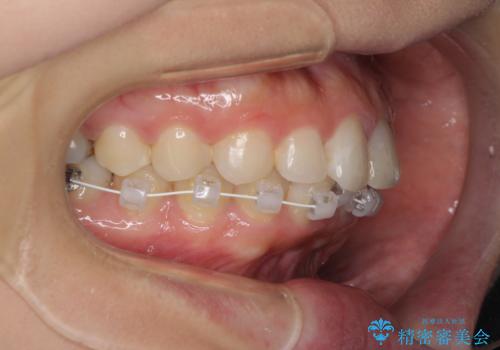

矯正治療の後戻り ガタガタになった前歯の部分矯正

- 以前の矯正治療の後戻りを気にして来院された患者様です。

下顎前歯にデコボコがあるため、ワイヤー矯正により改善することとしました。

もう少しデコボコを改善したかったのですが、ご本人の希望もあり、装置を除去しました。

後戻りを防止するため、舌側を細いワイヤーによる保定を行いました。